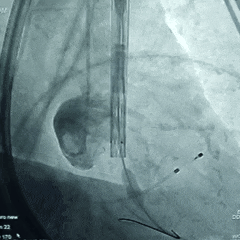

主动脉根部造影

18mm球囊预扩张